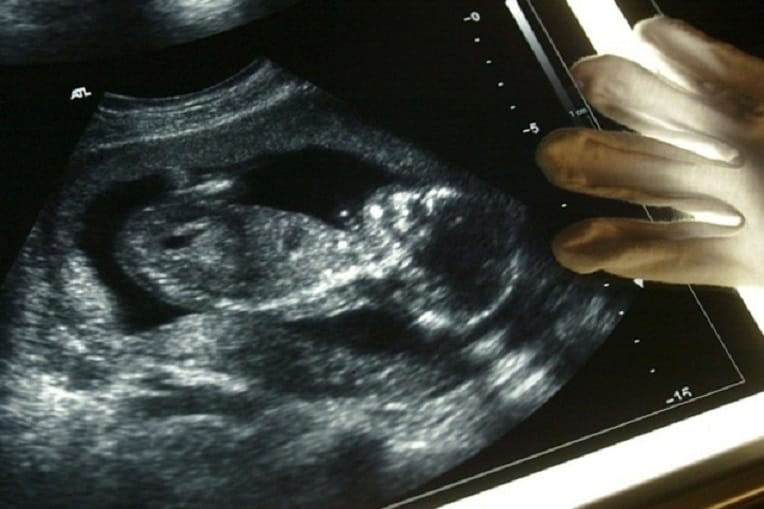

Un syndrome jusque-là inconnu et souvent incompatible avec la vie. C’est ainsi que les médias suisses décrivent la maladie rare qui touche les enfants et qui vient d’être découverte par des chercheurs de l’université de Lausanne.

Les résultats préliminaires des travaux menés par des chercheurs suisses ont ensuite été confirmés par des analyses effectuées sur 13 autres patients en Arabie saoudite, au Royaume-Uni, en Algérie, en Tunisie, aux États-Unis et à Singapour, poursuit la même source.

« La maladie en question a fait l’objet d’une publication dans lAmerican Journal of Human Genetics ce jeudi. Elle se manifeste par une malformation cérébrale sévère. L’enfant ne parle pas. Il ne marche pas. Une raideur articulaire et un pied-bot constituent d’autres symptômes. Dans les cas les plus sévères, le fœtus ou le nouveau-né ne survit pas », détaille 24 Heures.